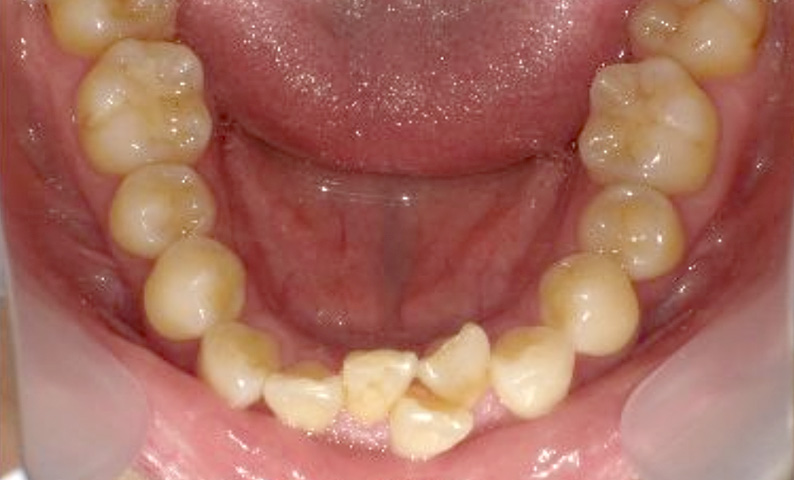

症例_003 上下顎の部分矯正

治療期間:12ヶ月金額:54万円+税男性八重歯前歯のガタガタ

| Before | After |